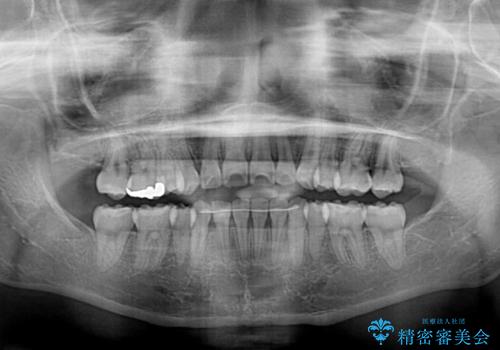

八重歯で正中が右にずれている ワイヤー装置での抜歯矯正で正中位置を改善

正中位置の改善に時間がかかることが予想され、2年半を治療期間の目標としておりましたが、20歳と年齢が若いこともあり、2年2ヶ月で治療を終えることができました。